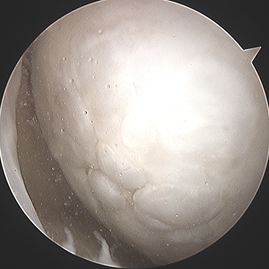

중기

카티스템 줄기세포 연골재생술(Cartistem)

제대혈 유래 줄기세포 치료제(카티스템)은 큰 연골손상이나 퇴행성 관절에서도 적용 가능하며, 더 질 좋은 연골 재생을 기대하는 수술입니다.

적응증 (누가 하는가)

- 연골 결손 크기가 비교적 크거나 깊은 경우

- 퇴행성 변화가 어느 정도 있는 경우도 적용 가능

- 미세천공술만으로는 재생이 부족할 것으로 예상되는 경우

- 나이가 있어도 가능

수술 방법 (어떻게 하는가)

1관절경 또는 최소 절개로 손상된 연골을 깨끗하게 다듬는다.

2이식부위를 형성

3줄기세포 제제(카티스템)를 병변 부위에 채워 넣고 고정 한다.

4봉합후 마무리 한다. 줄기세포가 더 질이 좋은 연골(유리연골 유사 조직)을 형성하도록 도와준다.

수술 전후 사례

수술 전

카티스템 수술

수술 후 1년